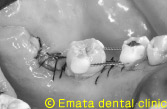

移植をおこないその移植歯を簡単な矯正(アップライト)し、今日移植歯と自分の歯の間にインプラント治療を行いました。

移植のオペです。 |